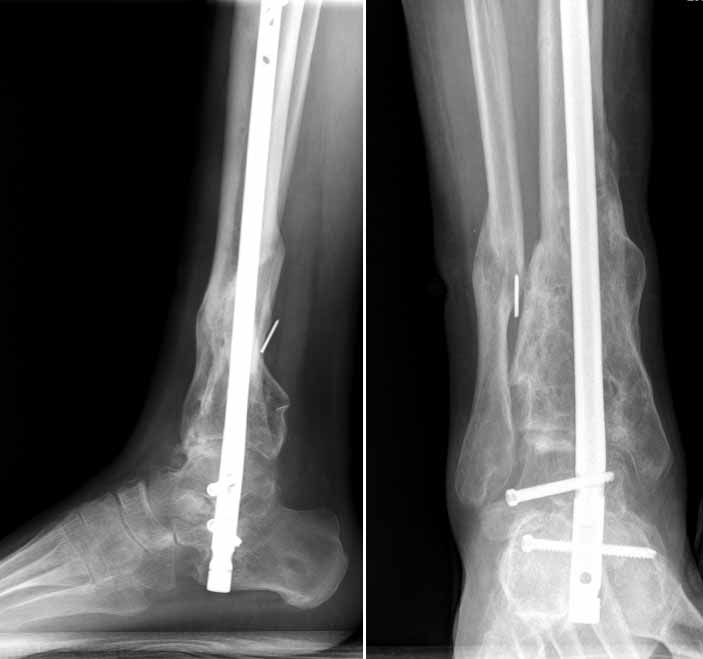

El médico que intervenga al paciente realizará una radiografía para identificar la posición del hueso fracturado. Es importante conocer la causa de la fractura, pues ayuda al médico a identificar los huesos dañados y cómo tratarlos. Una vez identificada, se recolocará el hueso en su posición original. Si el hueso es muy largo o se ha fracturado en más de dos partes, es posible que el médico realice una cirugía e introduzca un clavo de metal para consolidarlo. Este clavo será quitado una vez el hueso haya sanado.

Cuando los huesos se han desplazado en gran medida más allá de su posición original, se lleva a cabo una osteosíntesis, es decir, una cirugía para recolocar los huesos. Esto se hace mediante placas, tornillos, agujas o cerclajes con alambres.

Una vez recolocado el hueso, el médico aplica una escayola sobre la parte afectada y no la retirará hasta que el hueso se haya soldado, proceso que puede tardar de una o varias semanas dependiendo de la gravedad de la fractura.